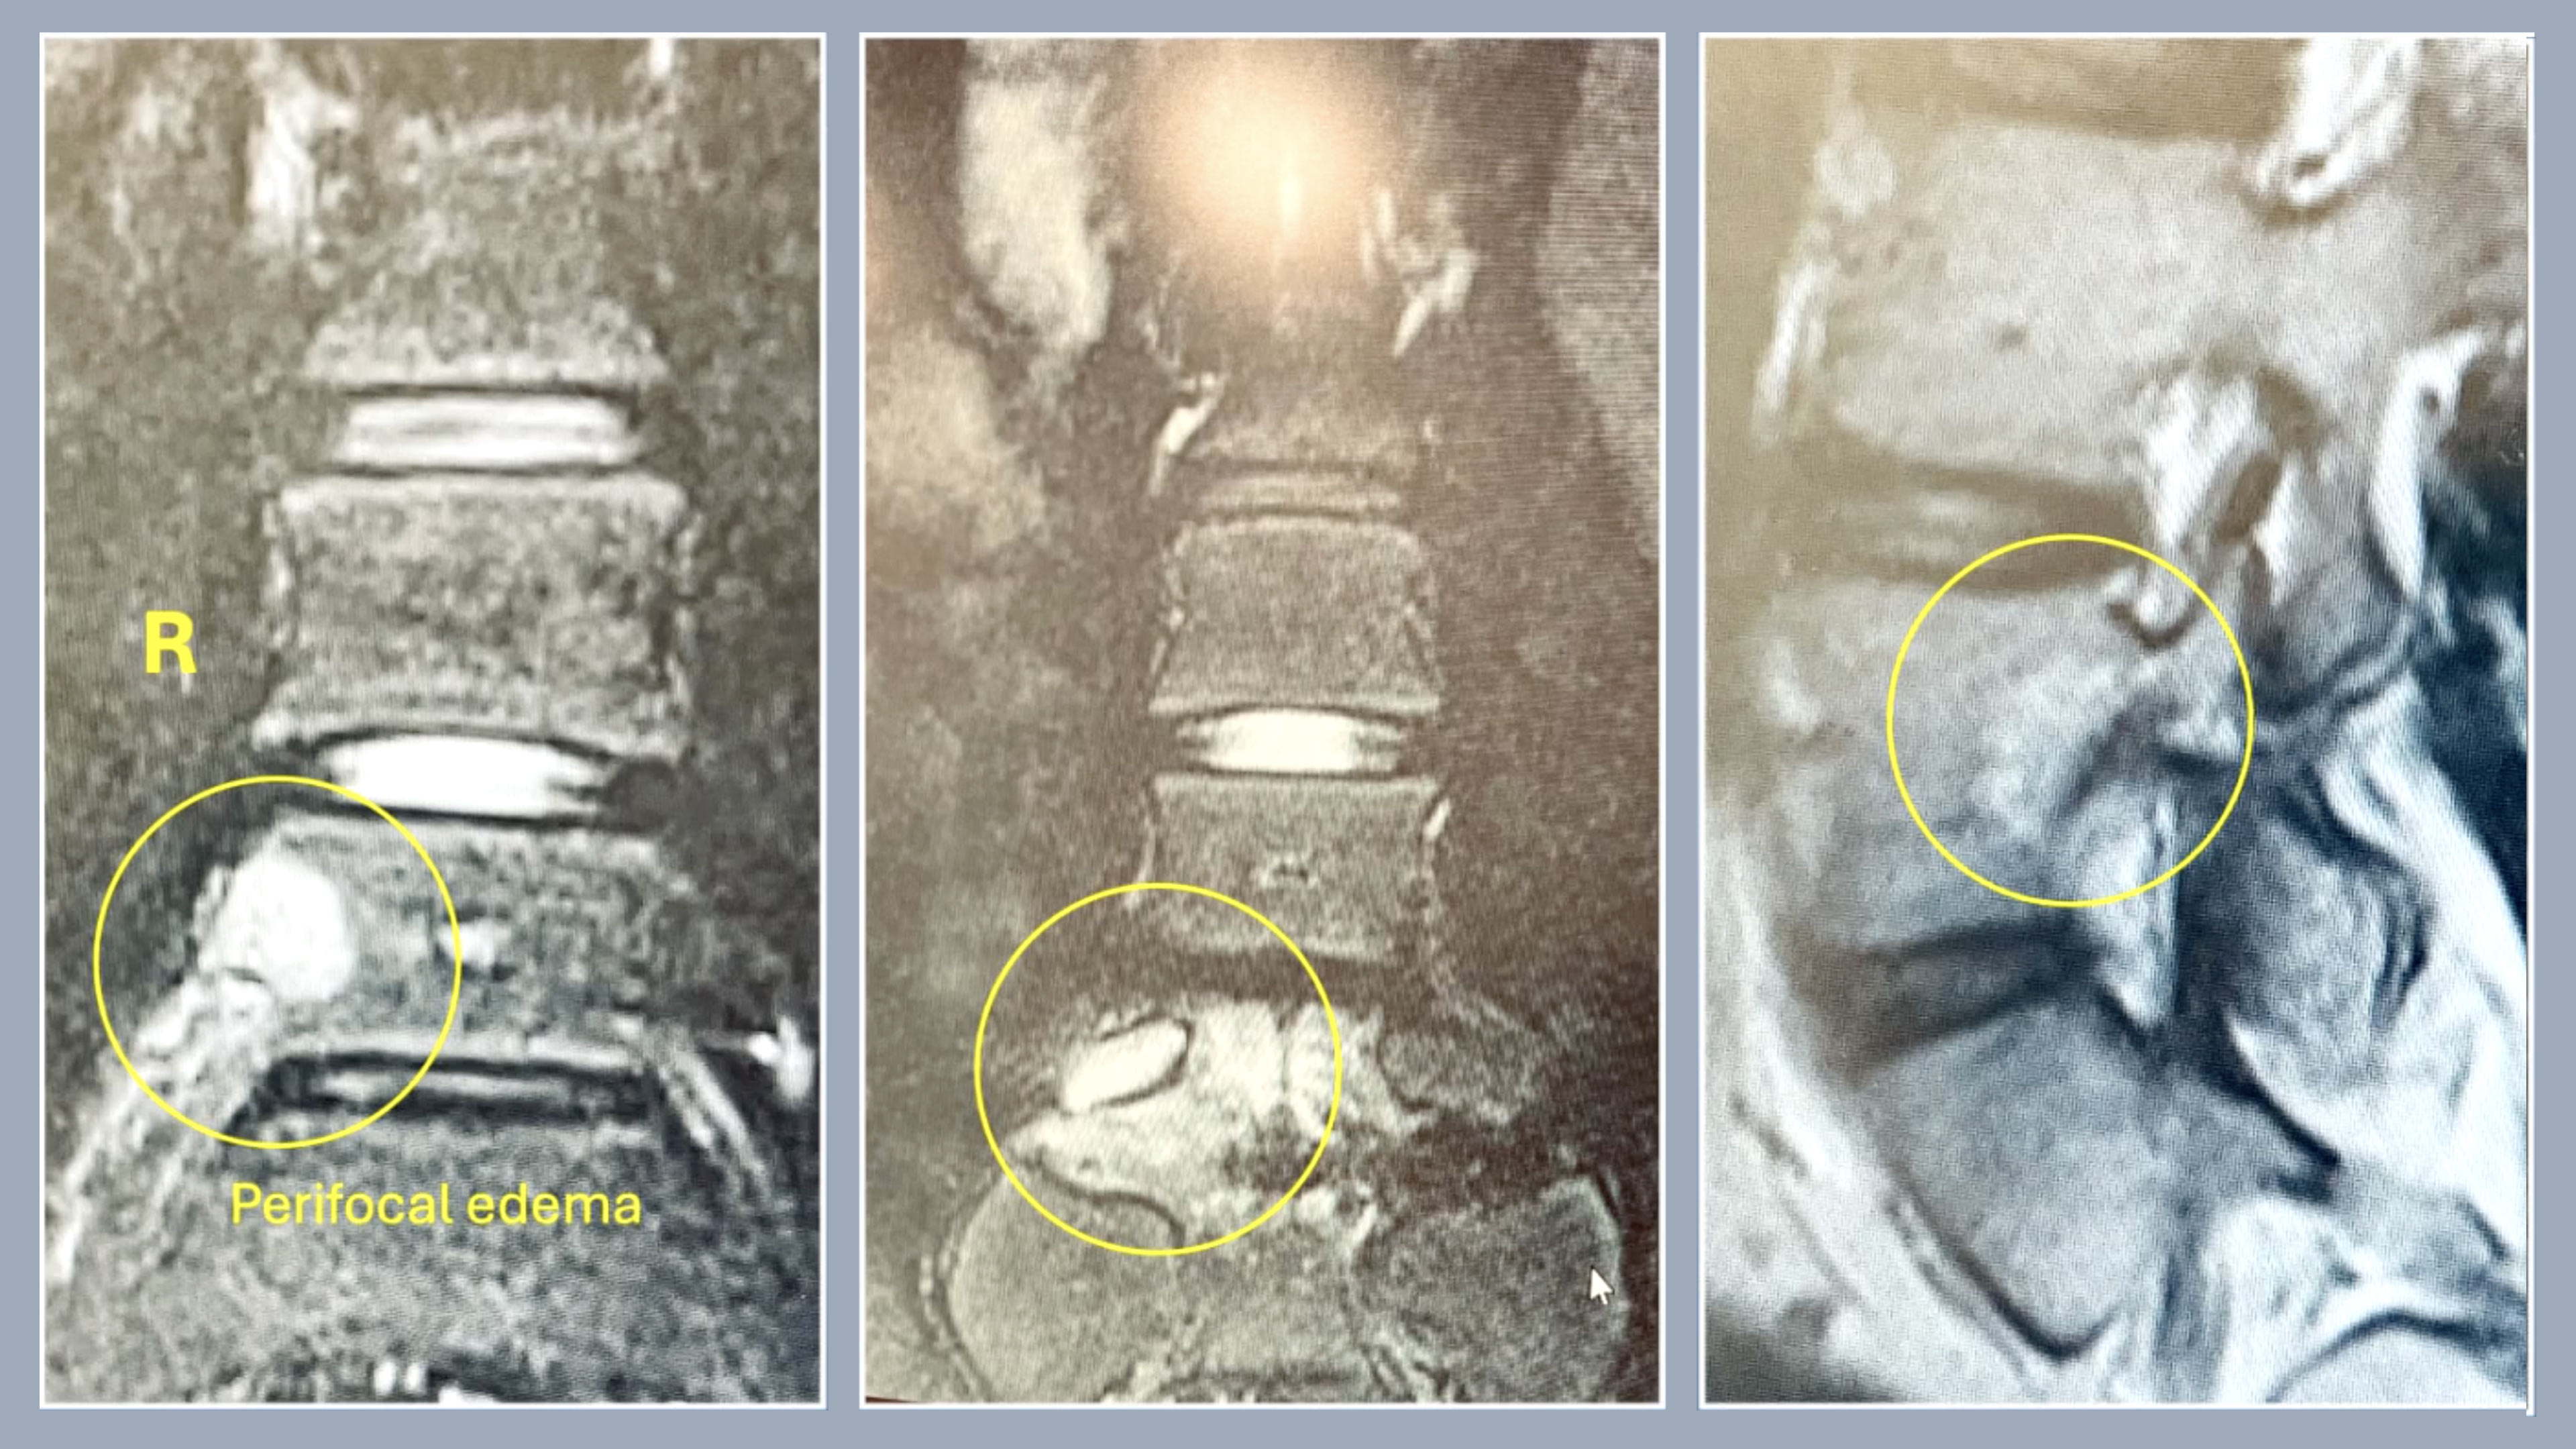

• Osteoid Osteoma of the L5 Vertebra (Interarticular portion on the right side)

Osteoid Osteoma of the L5 Vertebra (Interarticular portion on the right side)

Antaranyan Ara MD

Aebi Max MD, FRCSC

Wigmore Women's and Children's Hospital

Yerewan

Armenia

Project 24-008